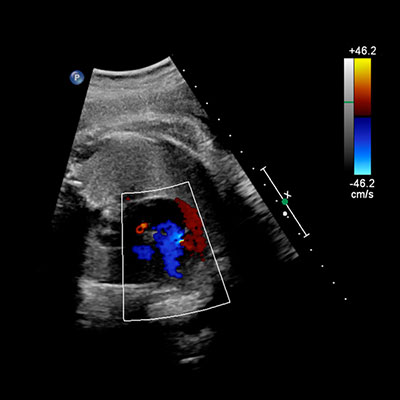

Checks blood flow in the placenta and umbilical cord.

Detailed assessment of the baby’s heart to detect congenital heart defects.